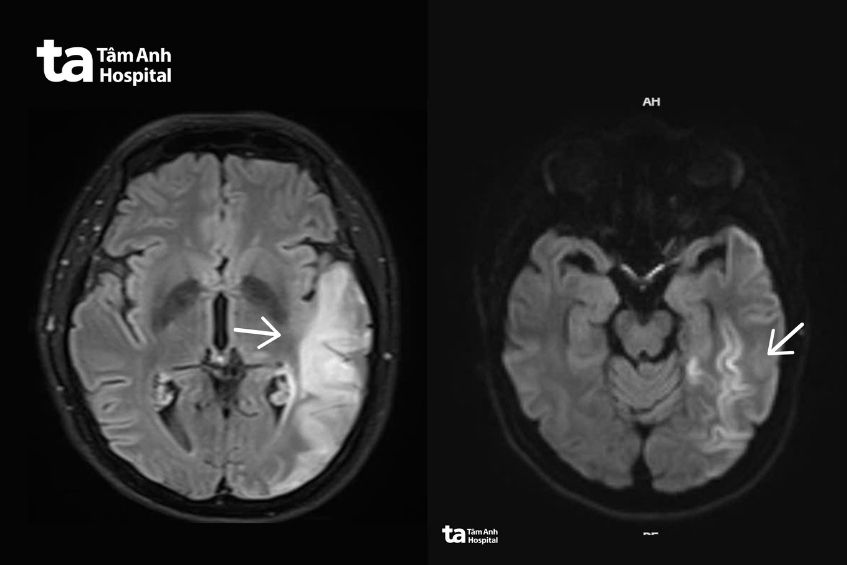

Chị Thu được gia đình đưa đến Bệnh viện Đa khoa Tâm Anh TP HCM cấp cứu trong tình trạng có các triệu chứng giống đột quỵ. BS.CKI Đặng Khắc Giáp, Trung tâm Khoa học Thần kinh, cho biết hình ảnh MRI 3 Tesla của chị Thu ghi nhận tổn thương não lan rộng bất thường, song không phù hợp với các đặc điểm điển hình của đột quỵ do tắc mạch hay viêm não.

Khai thác bệnh sử, người bệnh có thể trạng nhỏ con, gầy, kèm đái tháo đường khởi phát từ khi còn trẻ – những đặc điểm gợi ý rối loạn chuyển hóa năng lượng. Các xét nghiệm chuyển hóa chuyên sâu và chụp cộng hưởng từ phổ (MRI spectroscopy) ghi nhận bất thường rõ rệt trong quá trình oxy hóa năng lượng tại não, từ đó bác sĩ nghi ngờ bệnh lý ty thể.